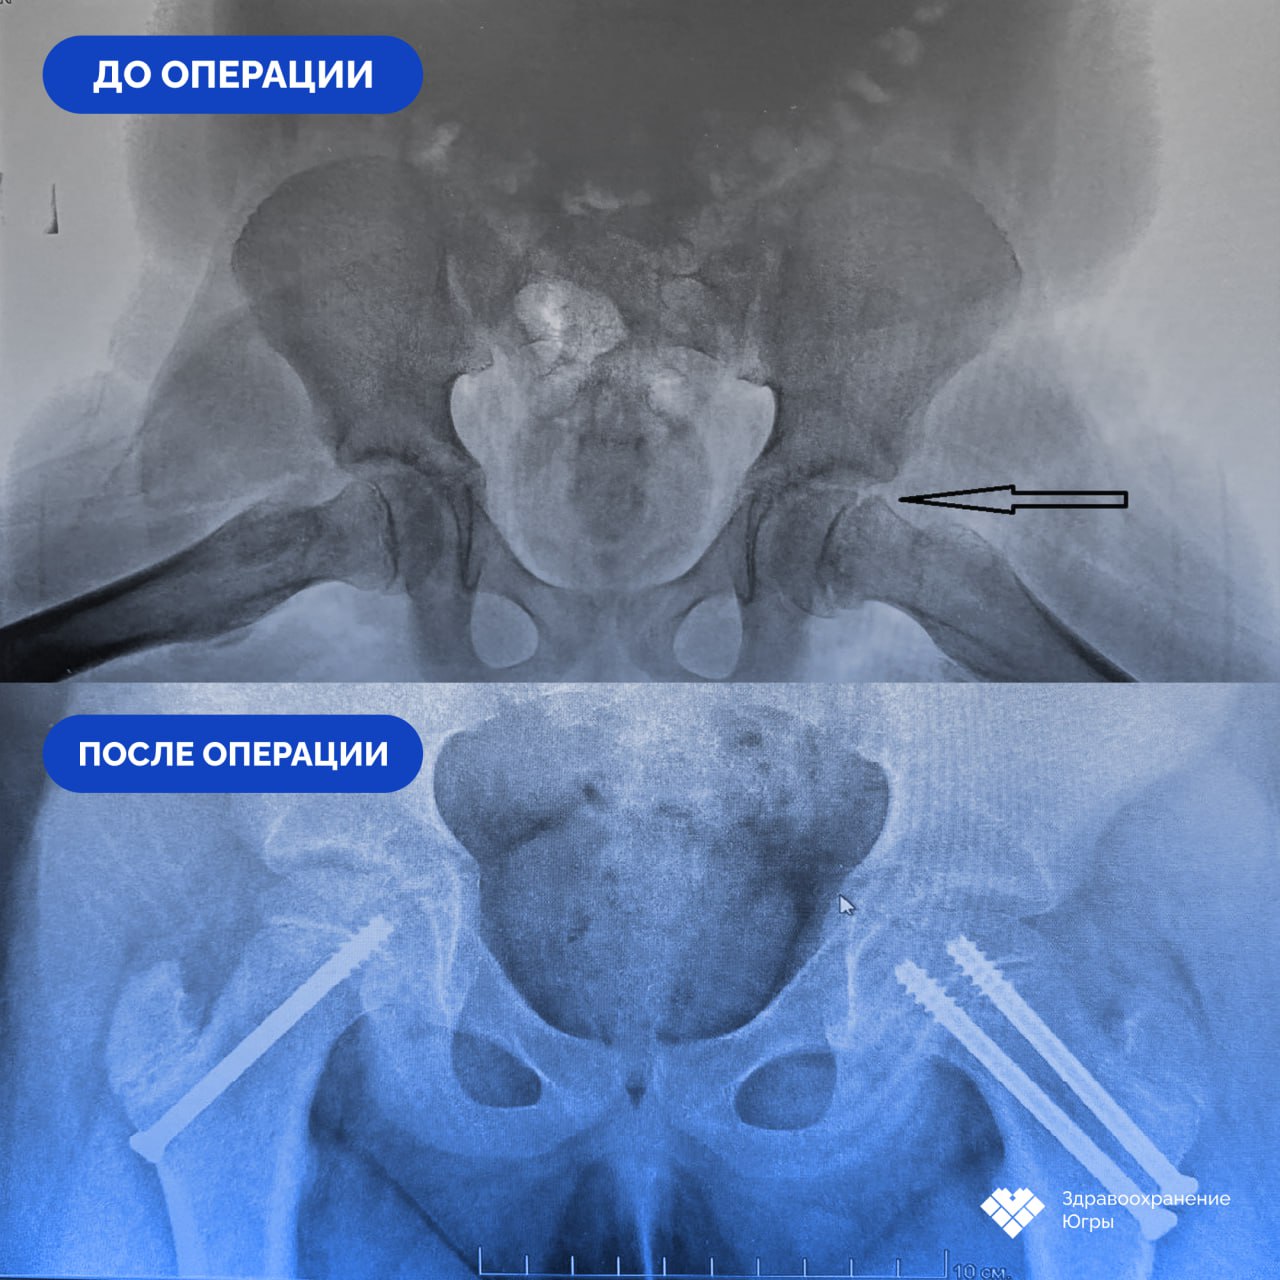

«Соскользнувшая» кость: нижневартовские врачи спасли двух подростков от инвалидности

Сначала — просто боль в бедре и легкая хромота. Два подростка из Нижневартовска и не подозревали, что причина их недомогания — заболевание, которое встречается лишь у пяти человек из ста тысяч. Врачи окружной детской больницы поставили редкий диагноз — юношеский эпифизеолиз.

«Вся причина в гормонах — они буквально размягчают кость, и головка бедра смещается, как бы соскальзывает. Без лечения это прямой путь к тяжелому артрозу и операции по замене сустава в молодом возрасте», — объясняет суть проблемы заведующий отделением Иван Тетюшев.

Медики действовали на опережение. Подросткам провели щадящие операции, которые не только устранили проблему, но и сохранили жизненно важное кровоснабжение сустава. Это стало залогом успешного восстановления.